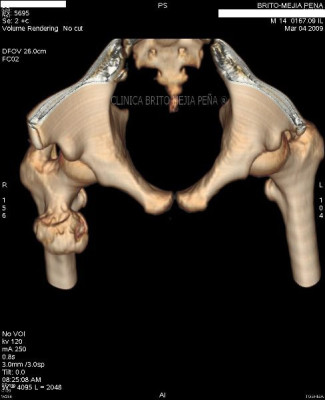

Exostosis femoral